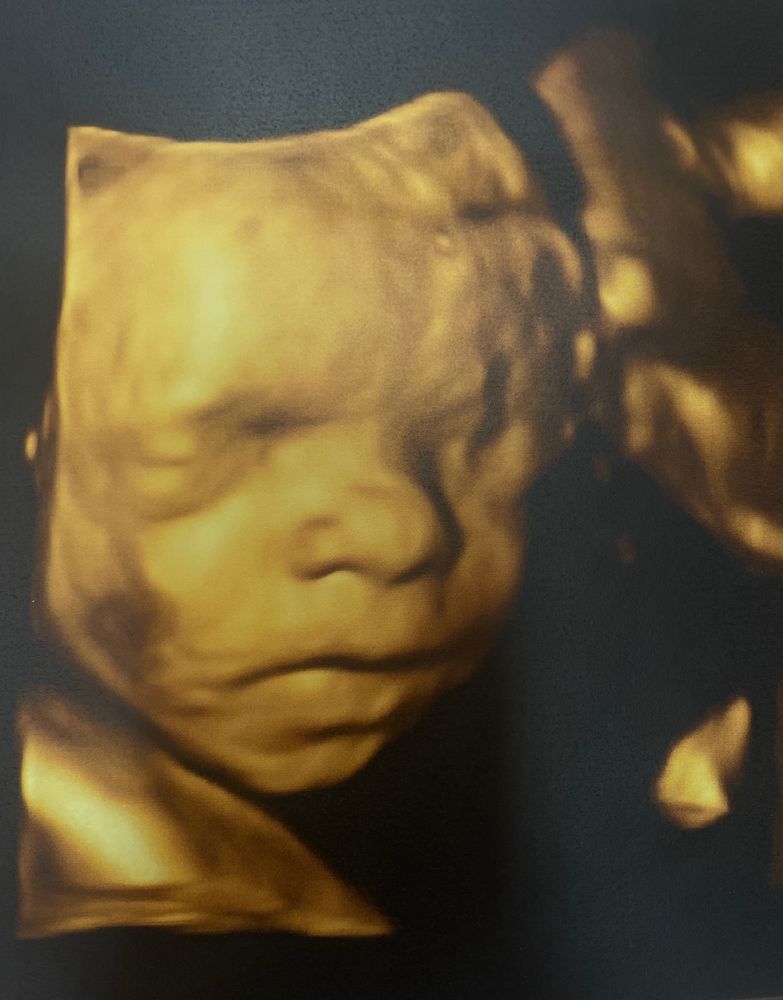

4Д УЗИ 🙏🏻

На 3-х предыдущих УЗИ дочь всегда лежала или затылком к датчику, или лбом в живот 😄 Поэтому я переживала, что 4Д снимки не получатся)) Ну, в начале так оно и было)) Ноги лежали на голове и закрывали лицо😄 Но позже мадам соизволила показаться ❤️

Собственно, нос, губы и вечно хмурые брови у нас в отца😄 Еще и в его день рождения намеревается родиться, по всей видимости)) срок по УЗИ, как всегда, на неделю больше. И если считать по нему (27нед 4 дня), то ПДР выпадает точно в день рождения мужа - 17.10👌🏻 Он, конечно, очень хочет поделиться с ней своим днем. Странный 😁